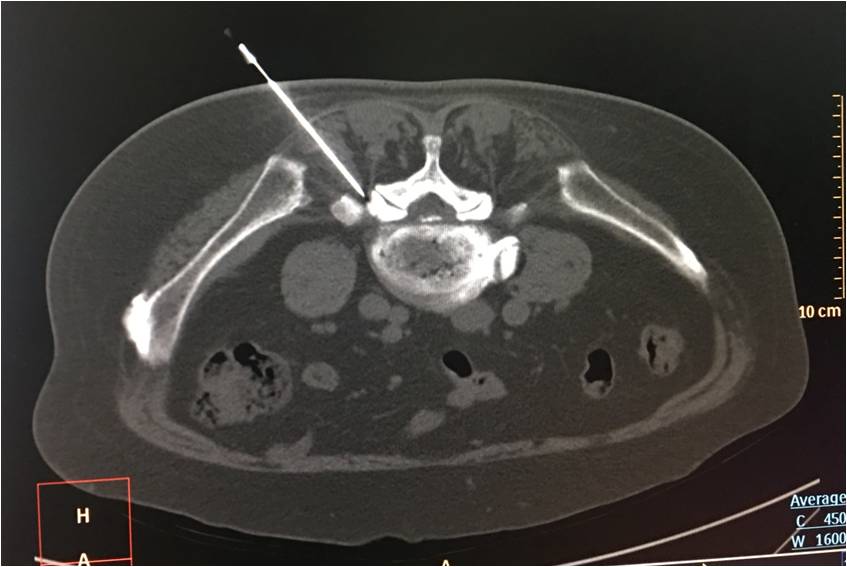

超声下引导体横下韧带针刀松解方法:固定好超声探头,穿刺点处给予0.5%利多卡因进行局部麻醉。用汉章牌3号1.0规格针刀(1.0mm×80mm),刀口与身体长轴平行,采用平面内穿刺,外侧入路,在超声实时引导下刺入皮下,缓慢深入,观察针尖准确触及横突上缘呈中强回声的窄薄层区,此时可感到针下为纤维样坚韧组织。

针刀技术融合了中医九针理论和解剖学理论,针刀既可以松解粘连,又能对局部组织起到一定的修复作用,相关文献均显示腰椎间盘突出症是针刀疗法理想的适应症。针刀作为一种闭合性手术,因损伤微小易于被患者接受,然而在闭合状态下,安全性和精准性是制约其应用的最大瓶颈。而根据超声在脊柱穿刺中的应用特点发现,腰椎横突附近相关组织可被超声探及并显示,从而实现穿刺的可视化,因此超声引导针刀松解体横下韧带具备了理论上的可行性。

由于体横下韧带的附着点位于横突根部上缘,因此应用超声定位相应横突为参照物,便可对针刀松解的靶点进行准确定位,从而实现对体横下韧带的精准松解。另外,在超声的实时监测下,松解深度得到准确控制,大幅度提高了操作的安全性,这使得针刀技术在后外侧型腰椎间盘突出症的治疗中充分发挥了其优势。而腰椎旁阻滞是治疗腰椎间盘突出症的常用疗法,通过在无菌性炎症的神经根周围注药,药物阻滞了C类神经纤维传导,稳定了细胞膜,同时糖皮质类激素抑制了前列腺素的合成,限制细胞和体液介导的自身免疫性反应,从而减轻了病变神经根的无菌性炎症,缓解了根性疼痛。将针刀与阻滞相结合,既缓解了神经的无菌性炎症,又减轻了对神经的物理性压迫,从而提高了疗效,进一步缓解了症状。